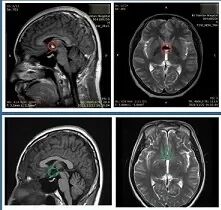

INC出国手术案例之研究生第三脑室海绵状血管瘤

“感谢INC和巴教授把我从绝望中解救出来,以后每一次的诗和远方我都会心怀感恩”

INC成功手术案例之中脑顶盖胶质瘤术后无复发,考上名校

“孩子术后恢复非常好,给我们病友群的病友起了一个很好的示范作用。我一些中脑胶质瘤患者现在都在存钱,万一需要手术大家还是想要去找巴教授。”